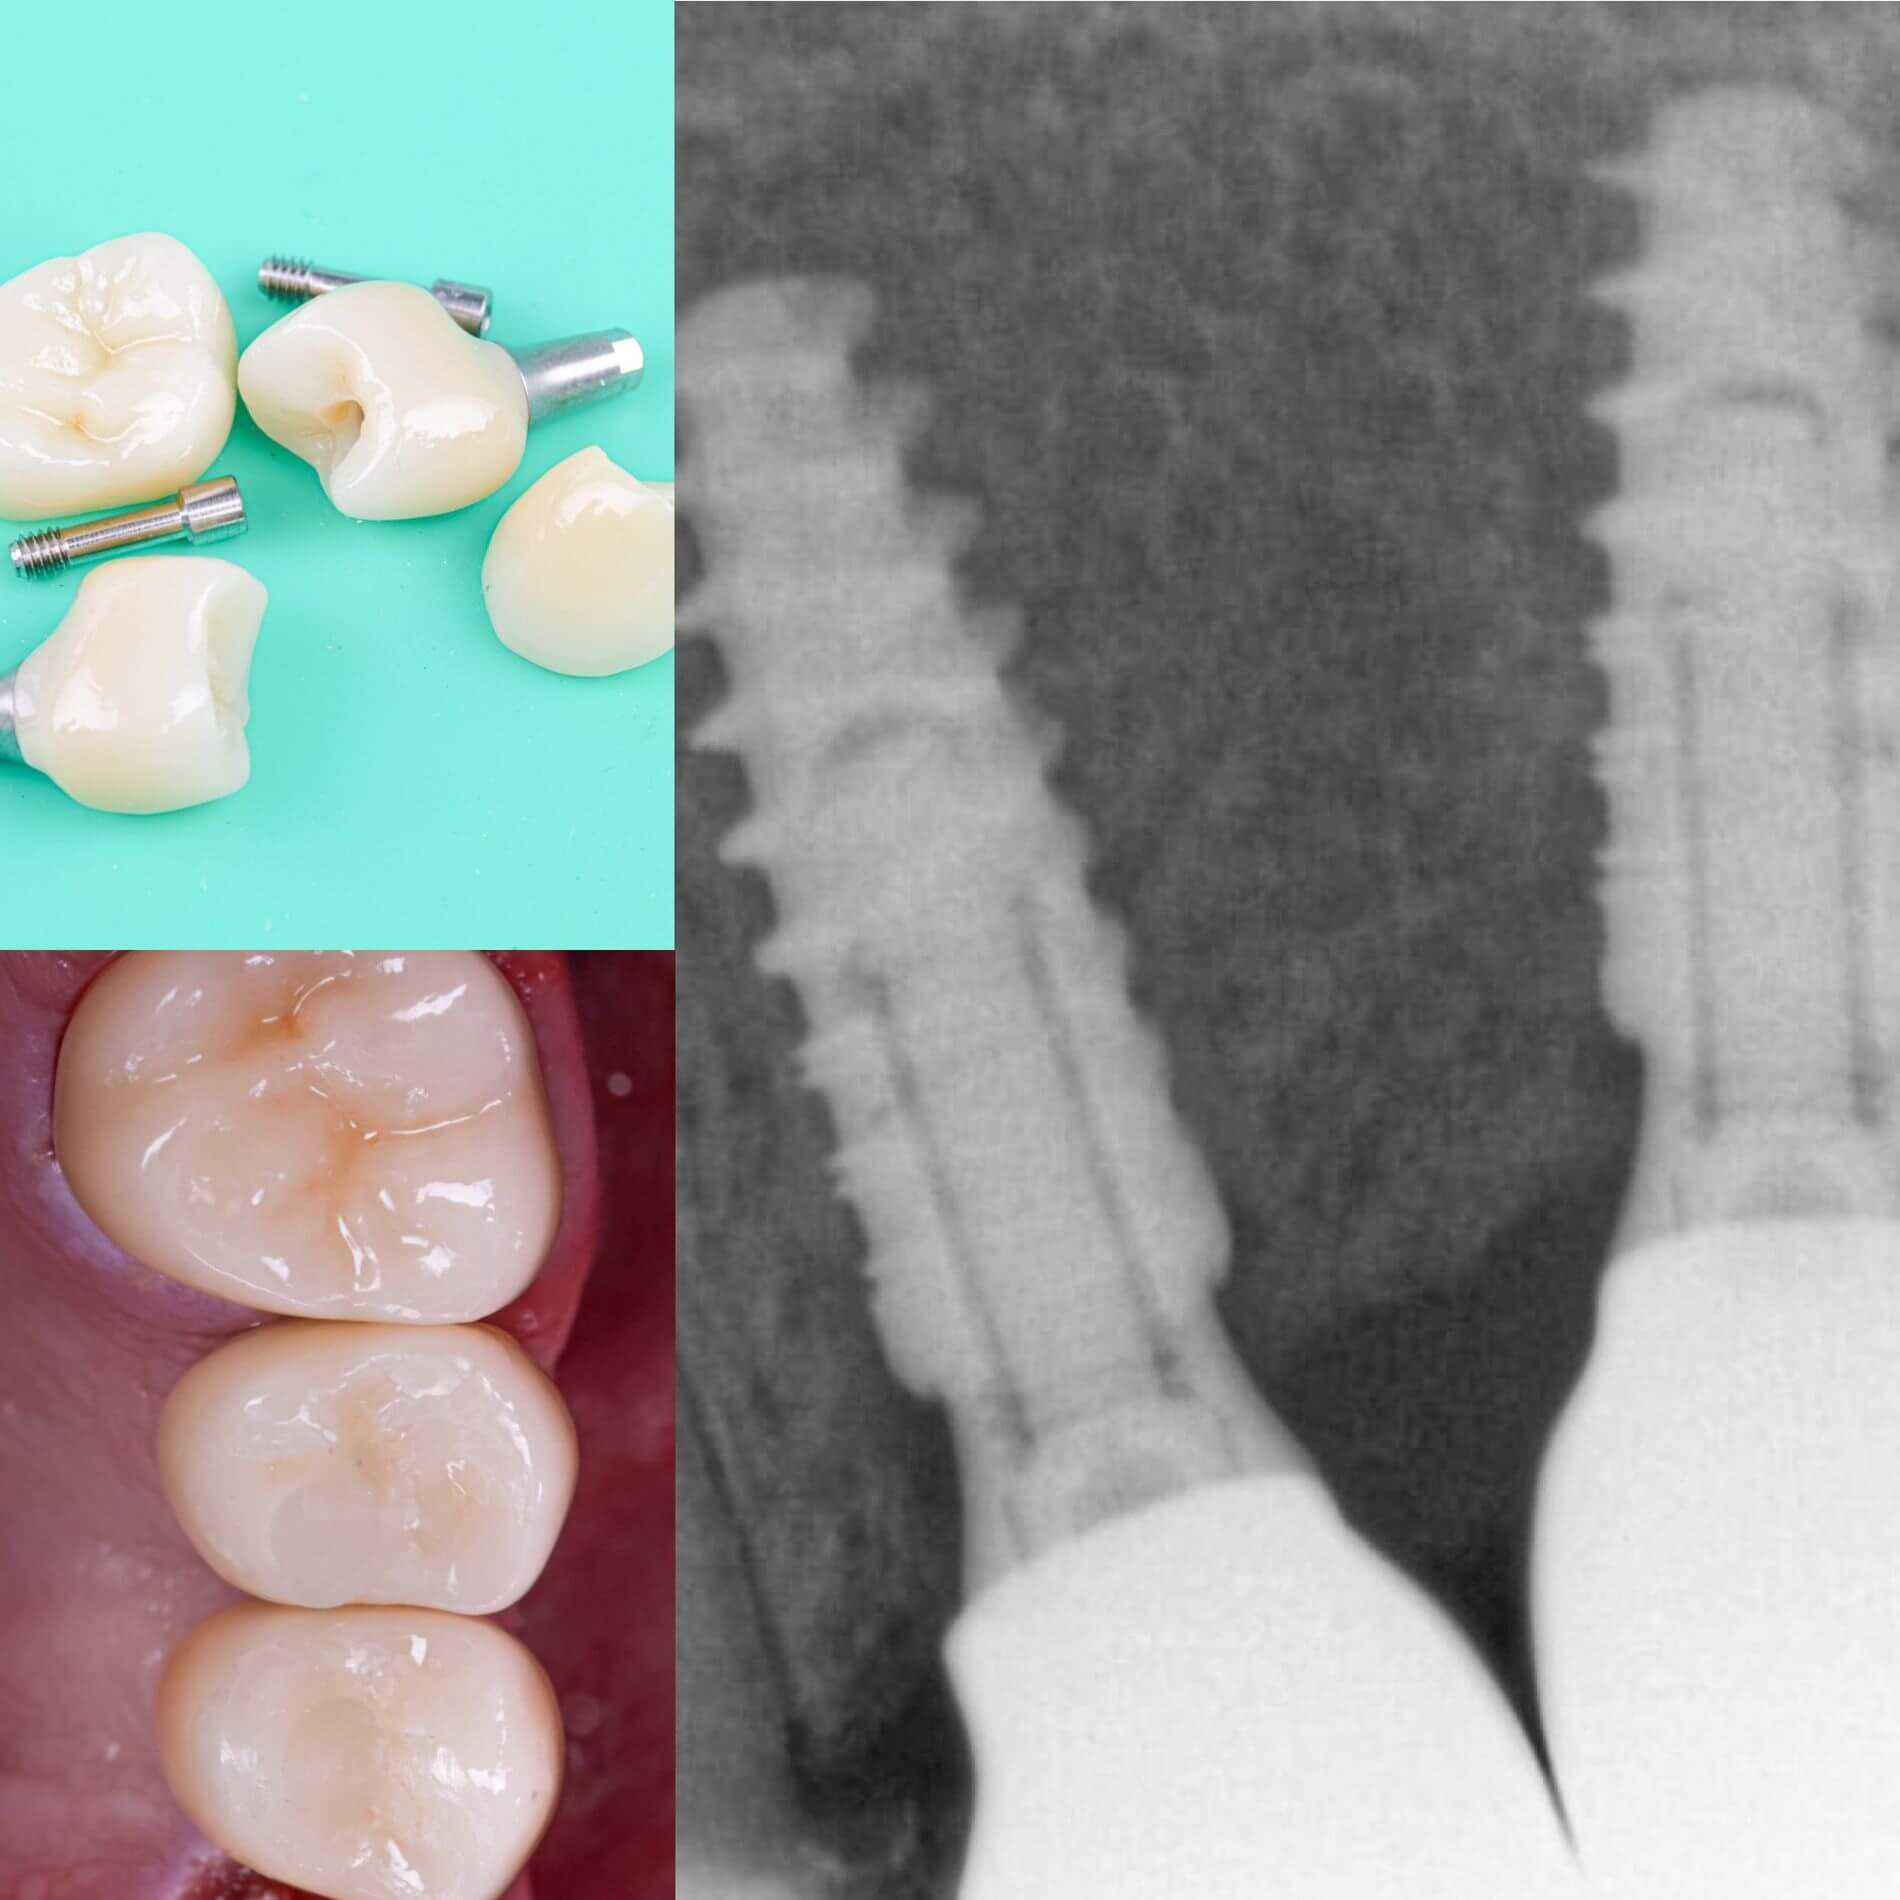

Галерея